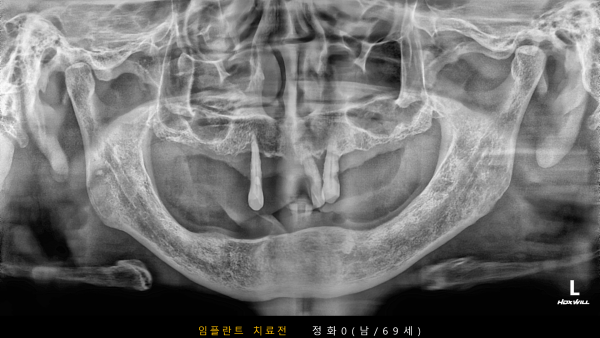

고난도 센터 | 남) 69세